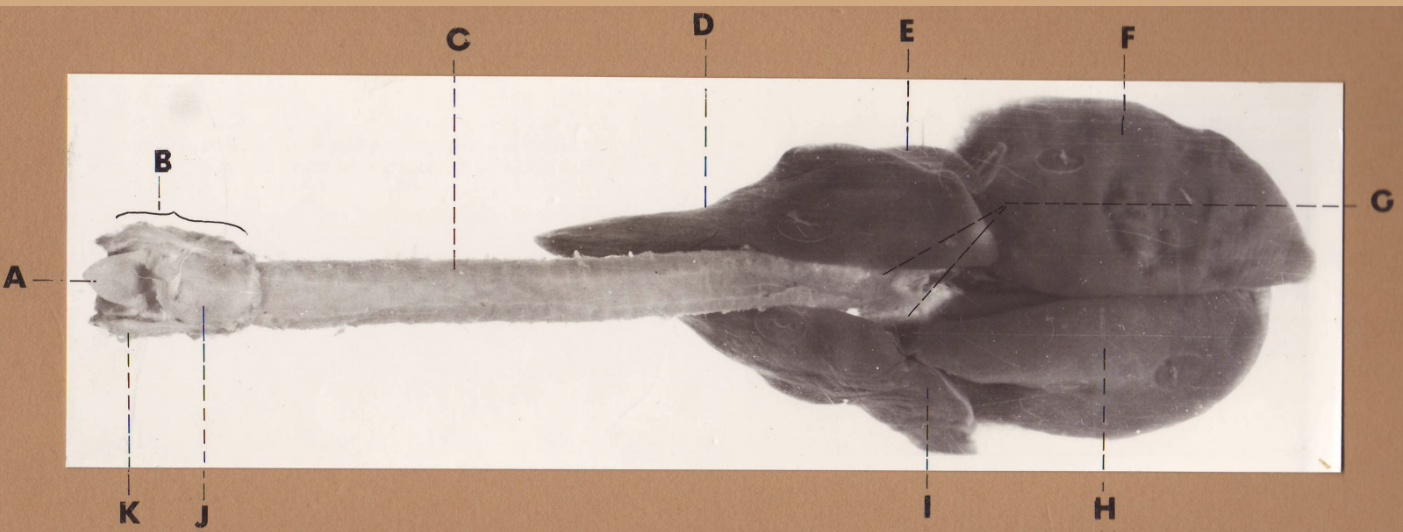

A

(cat larynx/trachea/lungs, dorsal)

epiglottis

B

(cat larynx/trachea/lungs, dorsal)

larynx

C

(cat larynx/trachea/lungs, dorsal)

trachea

D

(cat larynx/trachea/lungs, dorsal)

R cranial lobe

E

(cat larynx/trachea/lungs, dorsal)

middle lobe

F

(cat larynx/trachea/lungs, dorsal)

R caudal lobe

G

(cat larynx/trachea/lungs, dorsal)

primary bronchi

H

(cat larynx/trachea/lungs, dorsal)

L caudal lobe

I

(cat larynx/trachea/lungs, dorsal)

L cranial lobe

J

(cat larynx/trachea/lungs, dorsal)

cricoarytenoideus dorsalis m

K

(cat larynx/trachea/lungs, dorsal)

thyroid

A

(cat larynx/trachea/lungs, dorsal)

epiglottis

B

(cat larynx/trachea/lungs, dorsal)

larynx

C

(cat larynx/trachea/lungs, dorsal)

trachea

D

(cat larynx/trachea/lungs, dorsal)

R cranial lobe

E

(cat larynx/trachea/lungs, dorsal)

middle lobe

F

(cat larynx/trachea/lungs, dorsal)

R caudal lobe

G

(cat larynx/trachea/lungs, dorsal)

primary bronchi

H

(cat larynx/trachea/lungs, dorsal)

L caudal lobe

I

(cat larynx/trachea/lungs, dorsal)

L cranial lobe

J

(cat larynx/trachea/lungs, dorsal)

cricoarytenoideus dorsalis m

K

(cat larynx/trachea/lungs, dorsal)

thyroid